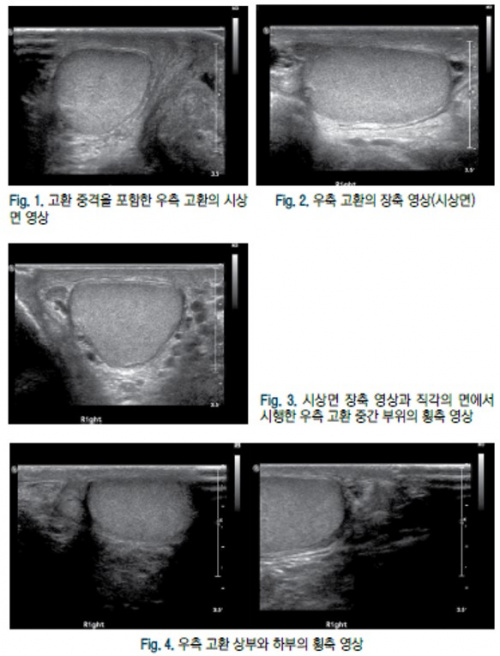

Ⅳ. 음낭 초음파검사 표준영상